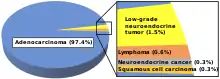

Histopathology

The histopathologic characteristics of the tumor are reported from the analysis of tissue taken from a biopsy or surgery. A pathology report contains a description of the microscopical characteristics of the tumor tissue, including both tumor cells and how the tumor invades into healthy tissues and finally if the tumor appears to be completely removed. The most common form of colon cancer is adenocarcinoma, constituting between 95%[75] to 98%[76] of all cases of colorectal cancer. Other, rarer types include lymphoma, adenosquamous and squamous cell carcinoma. Some subtypes have been found to be more aggressive.[77] Immunohistochemistry may be used in uncertain cases.